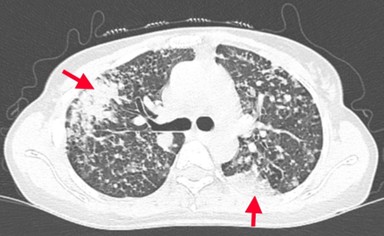

Case lâm sàng: Ứng dụng trí tuệ nhân tạo (Artificial intelligence – AI) trong chẩn đoán và điều trị sớm Ung thư phổi tại Trung tâm Y học hạt nhân và Ung bướu, Bệnh viện Bạch Mai

Theo GLOBOCAN 2022, ung thư phổi đứng đầu về số ca mới mắc (2.480.301 ca mới mắc chiểm 12.4%) và dẫn đầu số ca tử vong (1.817.172 ca tử vong chiếm 18.7%) trên toàn thế giới.  Tại Việt Nam tỷ lệ mắc ung thư phổi xếp thứ ba 13,5% lệ tử vong...